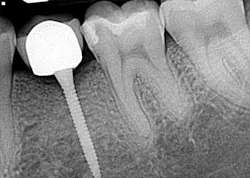

Hygiene. It can be agreed upon that if an implant can’t be kept clean, then the potential for failure and difficulties rise exponentially. A 90-degree angle between the implant and crown is virtually impossible to keep clean and maintain. As amazing as some hygienists are, it is impractical to expect that a curette can get into that space to clean it without making hamburger of the tissue. The implants were cemented on, so they are not easily retrievable. The emergence profile is nonexistent. Do natural teeth look like this? I would submit that when restoring implants, it is our job to mimic the shape and emergence profile of natural teeth as closely as possible. When we don’t, then we lose the inherent cooperation and benefits that the tissue can provide. To help the parents understand this concern, I showed them an example of a traditional implant vs. the “pumpkin on a toothpick” implant. The side-by-side comparison spoke for itself.

vs.